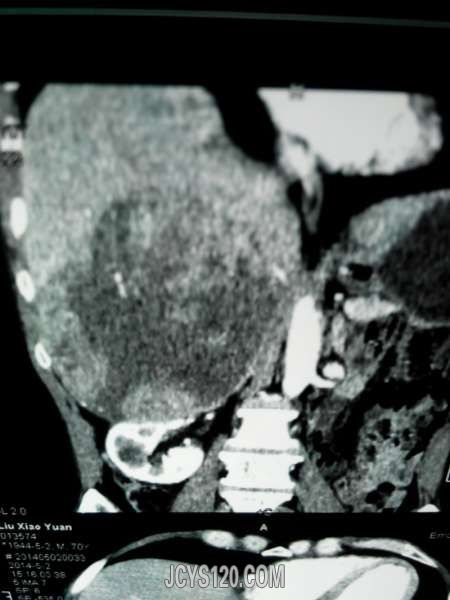

患者女性,70岁,体检发现,大家诊断什么病,怎么治疗。谢谢!